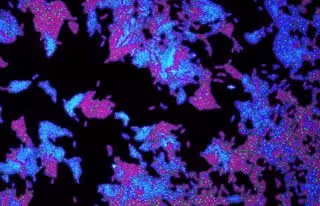

Células de la bacteria patógena Pseudomonas aeruginosa utilizada en el estudio

Células de la bacteria patógena Pseudomonas aeruginosa utilizada en el estudio - SEAN BOOTH